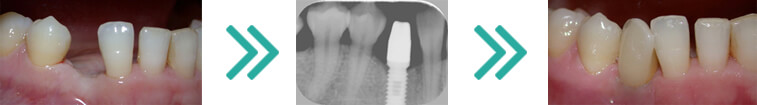

L’implantologia è quel ramo dell’odontoiatria che si occupa di interventi in grado di colmare quelle esigenze estetiche di pazienti che presentano denti mancanti e non vogliono ricorrere a ponti fissi e protesi, generalmente poco pratici. Scopo della chirurgia implantare è ripristinare la masticazione e l’estetica della bocca del paziente mediante il posizionamento di protesi su radici artificiali fissate all’osso della mandibola o della mascella, chiamate impianti dentali.

In poche parole viene inserita una “radice artificiale” nell’osso sottostante la gengiva e sopra di essa viene posizionata una corona in ceramica in totale armonia con la dentatura adiacente.